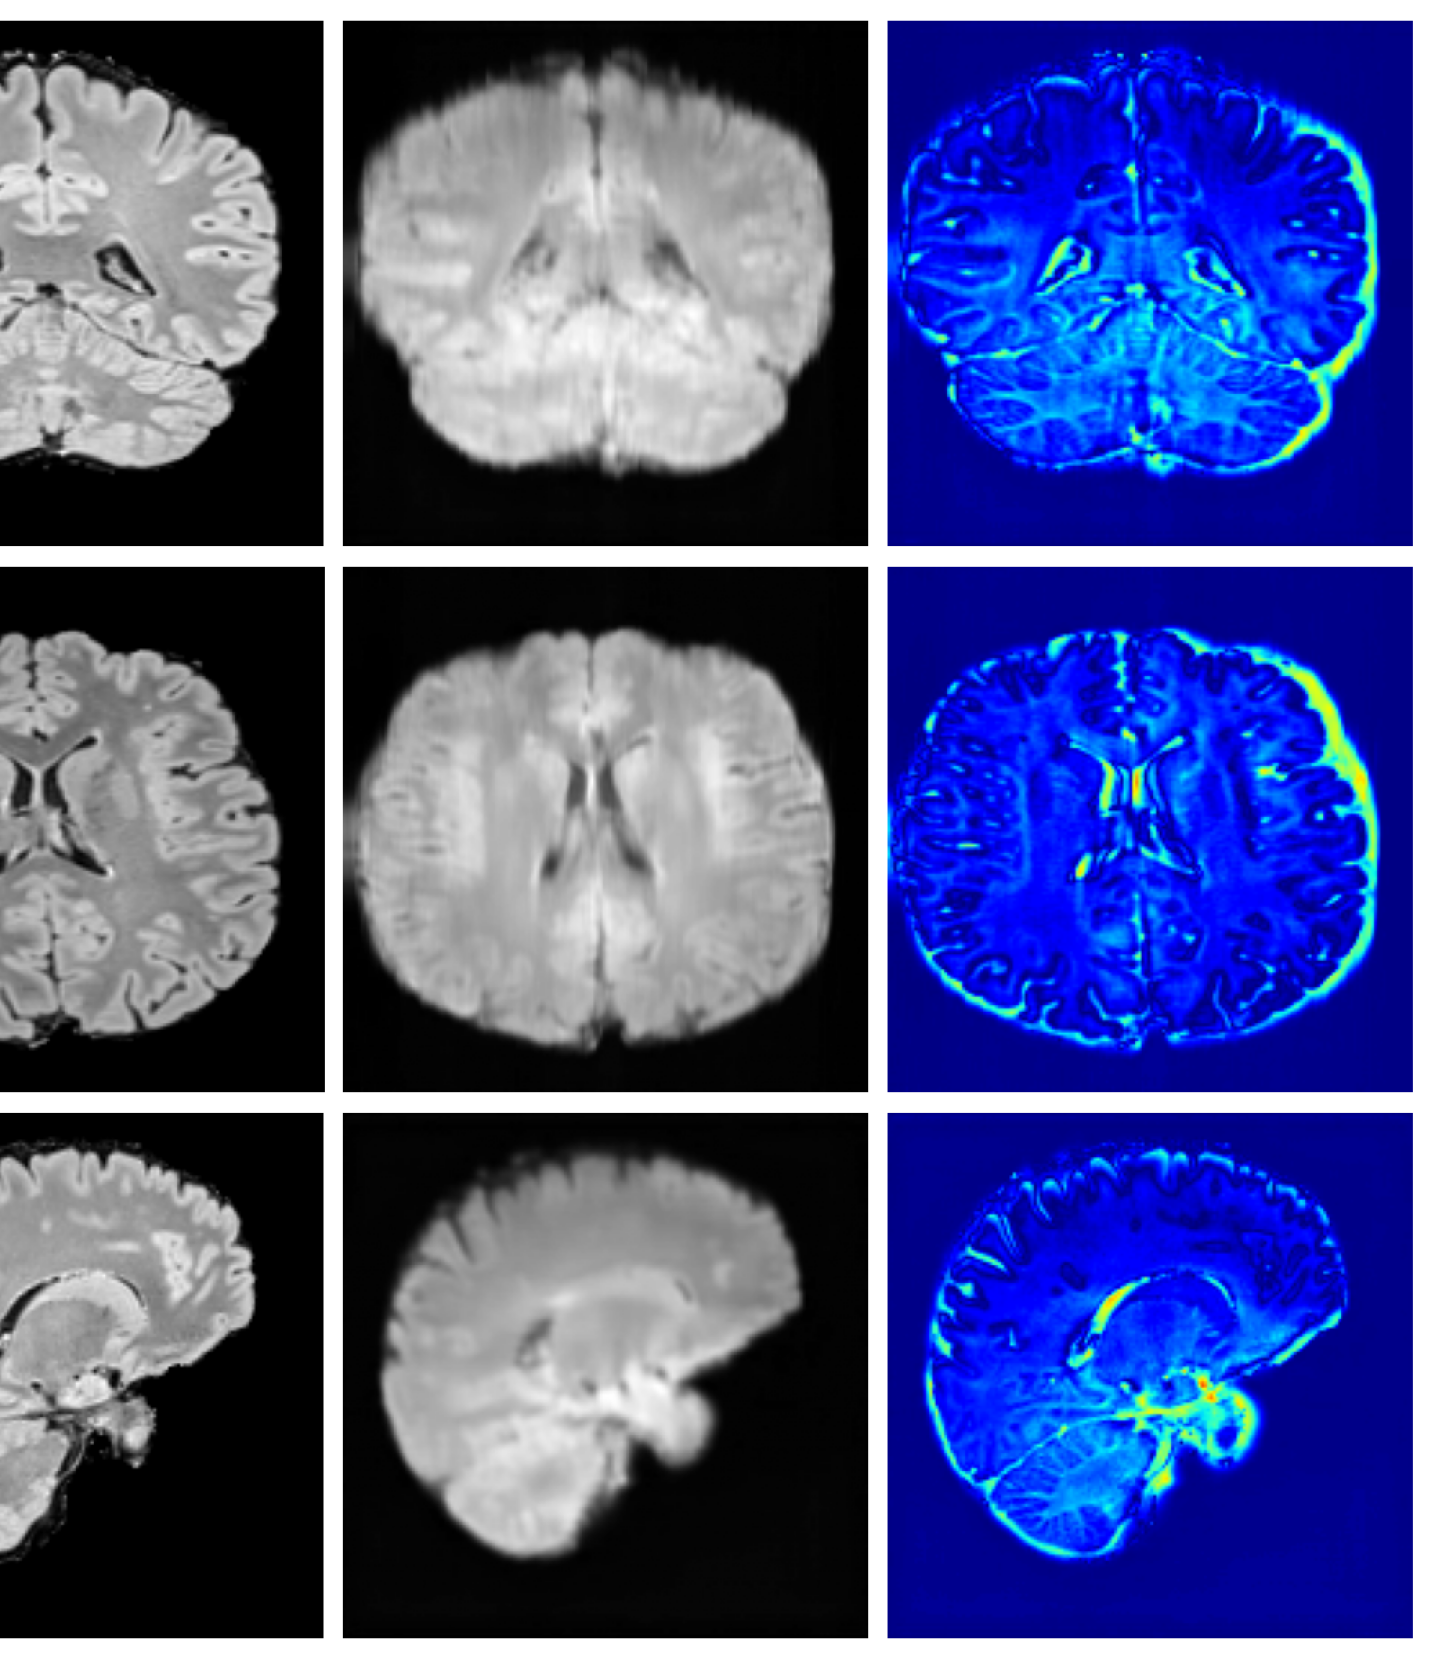

4.4 Image refinement results

The image refinement results (see Appendix A.10 for more examples) in Figure 4 highlight our framework’s ability to enhance outputs from existing methods. While SynthSR can inpaint disease regions, the resulting tissue often appears unrealistic. Our method further refines these areas, producing anatomically plausible reconstructions with more realistic surface structures.

A.10 Additional qualitative refinement results

Additional qualitative refinement results for subjects from the ATLAS dataset are given in Figure 14